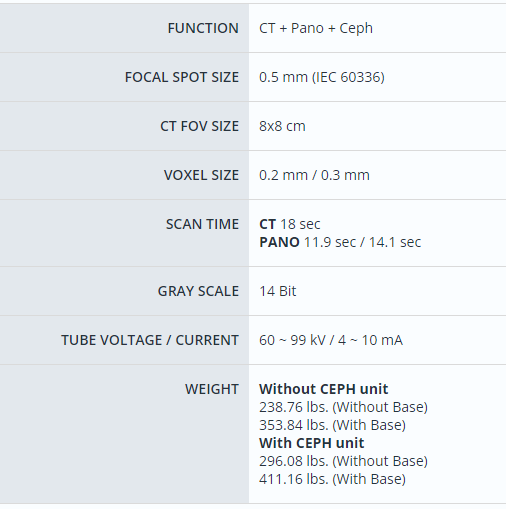

- Products Model: VAT-CBCT16

- Product Brand: Vatech America

Vatech A9 CBCT

The 'A9' is designed for dental clinics wanting to expand into high-value treatments like orthodontics and implant surgery. Vatech created the 'A9' to make CT technology more affordable for clinics, helping them manage the high costs. It also meets the growing demand as more clinics adopt CT technology.

The A9 provides high quality panoramic and CBCT images by combining image processing and accumulated experience in dental imaging from Vatech's image clarity expertise. This will increase your diagnostic accuracy for improved treatment planning and patient satisfaction.